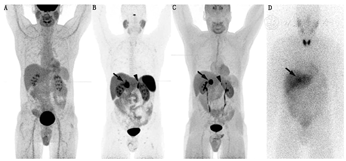

123I-MIBG更适合用于显像[8],131I-MIBG更适合用于治疗前剂量测定或记录治疗后的生物分布。给药活性和剂量测定见补充材料表1。服用MIBG后,血液清除迅速,2~5 d全身排泄超过80%,主要通过肾排泄[9]。正常的生物分布包括肝、肺、心脏、脾和唾液腺的摄取(图1)。肾上腺通常也有摄取,在CT无异常的情况下,摄取等于或低于肝水平被认为是生理性的。

给药活性和剂量测定见补充材料表1。18F-FDOPA的药代动力学和生物分布研究显示其血液清除迅速[29],大多数肿瘤摄取发生在给药后30 min内[27]。基底神经节、肝和胰腺有生理性摄取(图1),肠道和食管见轻度摄取。18F-FDOPA在正常肾上腺中为低摄取(平均SUVmax,1.9),与123I-MIBG的显著摄取相比,这对肾上腺肿瘤显像更为有利[30]。

(1)患者准备、给药、药代动力学、生物分布及剂量测定。18F-FDG显像流程指南适用于PCC或PGL患者[25,36]。患者准备、给药活性和剂量测定结果见补充材料表1。正常的生理性摄取包括脑、泌尿系统、肝和脾,另有不同程度的心脏和肠道摄取(图1)。正常肾上腺的摄取低于肝(平均SUVmax,1.6)[14]。

(1)患者准备、给药、药代动力学、生物分布及剂量测定。68Ga-DOTA-SSA的显像流程指南已发布[25,26]。在显像前中止SSA治疗的建议可能不是必要的(见补充材料表1)。给药活性、特殊注意事项和剂量测定见补充材料表1。68Ga-DOTATATE/TOC的生物分布已有报道[48],其在血液中快速清除。显像剂主要经肾清除,在脾、肾、肾上腺、垂体和肝中显著摄取(图1),不同类似物间的差异很小[48]。大多数肿瘤摄取发生在注射后30 min。唾液腺和甲状腺可见低摄取。68Ga-DOTATATE在正常肾上腺的SUVmax高于良性腺瘤(范围16.4~20.3与6.3~11.8)[49]。相比之下,PGL的平均SUVmax为94.2(范围33.15~155.2)。